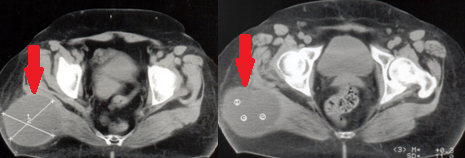

Αξονική τομογραφία κοιλίας. Φεβρουάριος 2017. Εμφανίζεται η υποτροπή του οπισθοπεριτοναϊκού αγγειοσαρκώματος (κόκκινα βέλη)